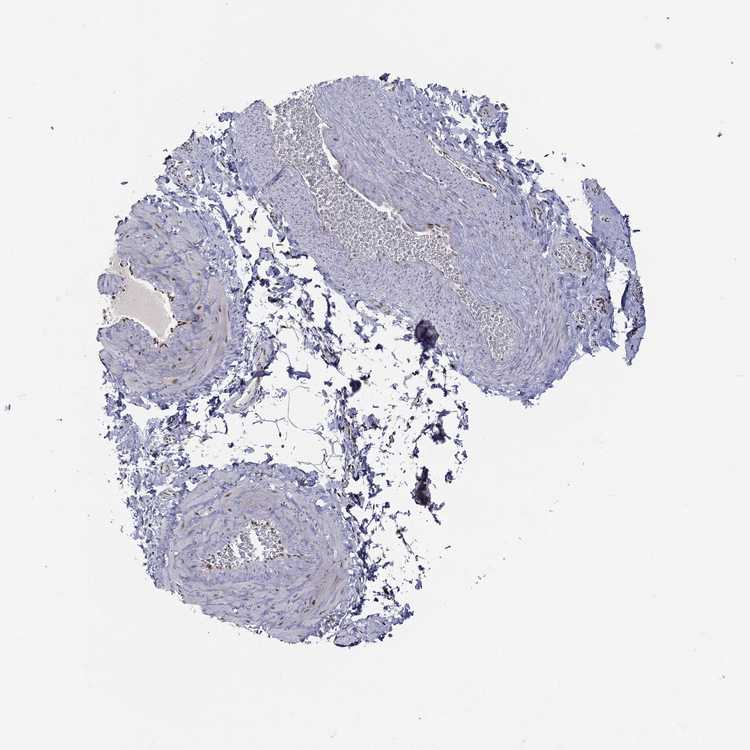

SOFT TISSUE 1 - Antibody stainingi

Antibody staining in the annotated cell types in the current human tissue is reported as not detected, low, medium, or high, based on conventional immunohistochemistry profiling in selected tissues. This score is based on the combination of the staining intensity and fraction of stained cells.

Each image is clickable and will lead to virtual microscopy that enables deeper exploration of all samples and also displays staining intensity scores, fraction scores and subcellular localization as well as patient and tissue information for each sample.

Antibody CAB058686Antibody CAB079943

Fibroblasts MediumNot detected

Peripheral nerve -Medium

SOFT TISSUE 2 - Antibody stainingi

Antibody HPA027524Antibody CAB058686Antibody CAB079943

Fibroblasts -MediumNot detected

Peripheral nerve Not detectedMediumLow